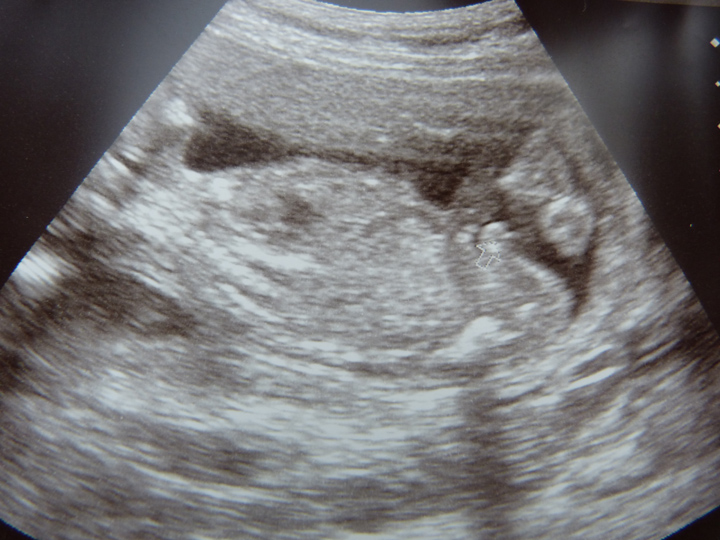

19 weeks u/s

Thanks Rockstar, in the second picture the tech put an arrow pointing at the boy bits, and in the third picture I think the winky is the bobbly bit inbetween the legs but I'm confused as there are kind of two together and then a third mark to the right. Maybe that is part of the foot or something else?

I was really hoping for a clear potty shot but she didn't really understand what I mean and the only pictures we saw were sideways ones

I see a side view of boy parts in the 2nd pic. Congrats!

That's a boy without a doubt! Nice side view of boy bits (scrotum and penis)!!